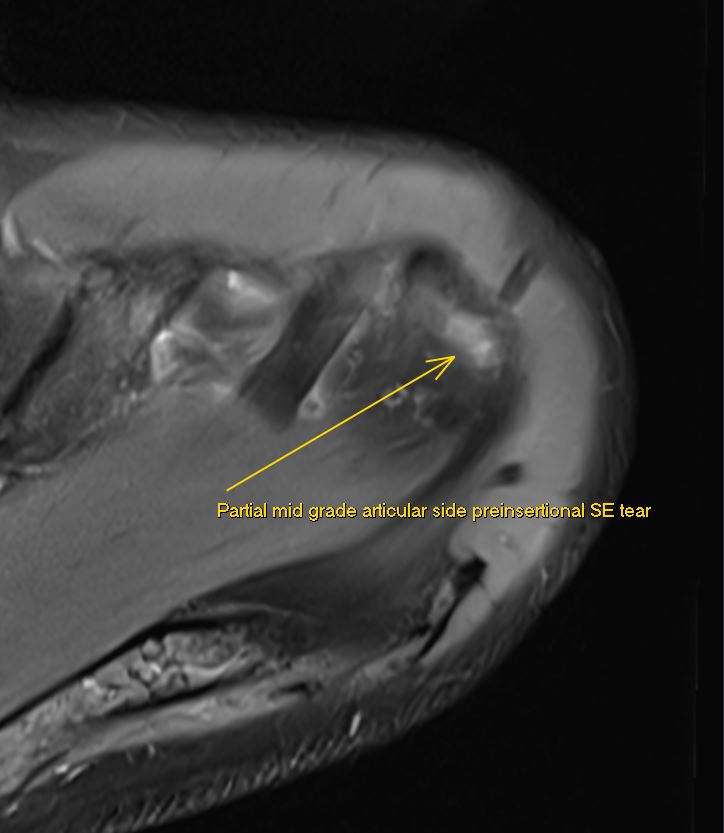

JuanMiranda@themskarchive·

5/6/2024. 👌 Thrilled to have improved MRI protocols with my teammate @pepelermarx! This #shoulder MRI clearly shows a preinsertional partial articular-sided mid-grade supraspinatus tear in three planes 💪. #MRI

JuanMiranda tweet mediaJuanMiranda tweet mediaJuanMiranda tweet media